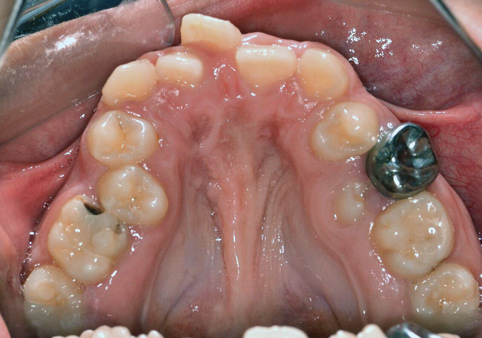

Fig 15. Nance arch (maxilla).

Figure 15

In cases of premature loss of primary teeth or missing permanent teeth, space maintenance is crucial.42 Possible causes of such tooth loss include caries, trauma, or a congenital disorder. If proper spacing is not maintained, mesial tooth drift may occur,43,44 which can lead to impaction or ectopic eruption of permanent teeth, as previously discussed. Various designs of space maintainers are available, depending on the location in the mouth that needs space preservation. Common devices include the Nance arch for the maxilla (Figure 15), a lower lingual holding arch for the mandible (Figure 16), and a band and loop or distal shoe for unilateral cases of space loss (Figure 17). Band and loop appliances seem to have the highest longevity intraorally; generally, unilateral devices fare better than their bilateral counterparts.45